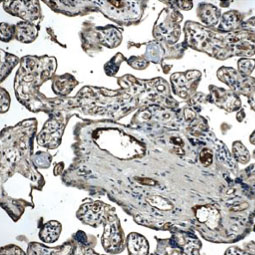

| 血管生成就是从预先存在的脉管系统中产生新血管,这是由促血管生成因子和抗血管生成因子输入严格控制的复杂过程,在正常成人中,这些诱导剂和抑制剂之间的平衡保持一种静止状态,尽管如此,它仍然能够响应因伤口、缺氧或炎症引起的微环境破坏而产生快速变化,在各种慢性病理状况和肿瘤中,这种平衡的扰动可导致不适当的血管生成或新血管形成,潜在的血管生成机制很复杂,但是调节这一过程的临床重要性意味着,这将仍然是引人注目的动态研究领域。 GeneTex提供广泛的研究抗体来支持血管生成的研究,请查看下面热门研究产品,或点击按钮以查看更多产品信息。 |